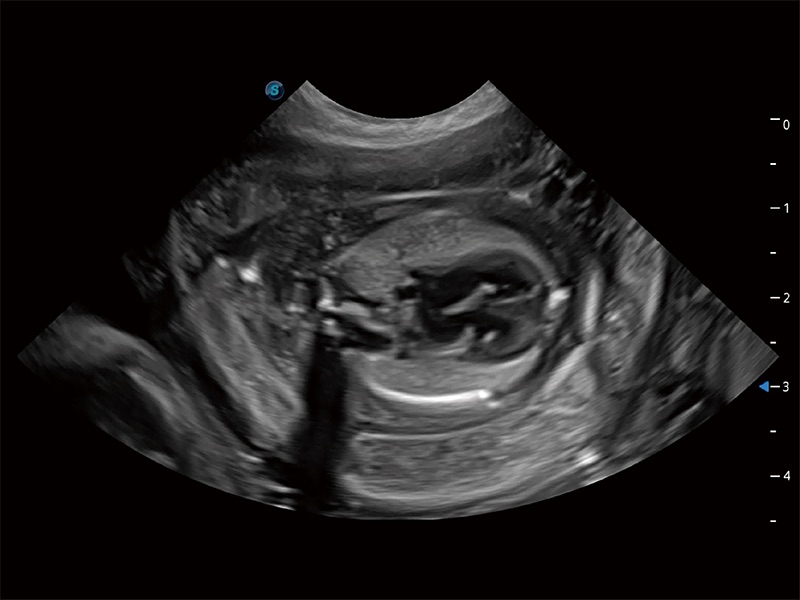

动物是人类最亲密的朋友和最值得信赖的伙伴。1xBET也一直致力于探索动物专用的超声影像解决方案。全新推出的ProPet系列,是1xBET在动物超声影像智能化、专业化、精准化的一次跨越式革新。动物不能用言语来表述自己的不适,通过超声影像,ProPet系列搭建了动物医生与不同物种沟通的“桥梁”,为动物医生注入了“治愈之力”。 ProPet 80 是1xBET匠心打造的一款高端动物专用彩超,采用性能卓越的全新硬件架构,极大提升超声系统的运行效率和数据处理能力,帮助动物医生从容应对日益增多的挑战性病例和日益多样化的临床需求。

高性能和先进的临床应用工具可以为动物医生提供临床信心。ProPet 80 搭载了先进的腹部和浅表应用工具,帮助医生在日常临床实践中发挥前所未有的作用。

ProPet 80 专为动物医生设计,对不同的动物体型和生理结构作出了针对性的优化。通过动物影像专用软件,可满足个性化的应用需求,帮助动物医生获得更精确的诊断数据。